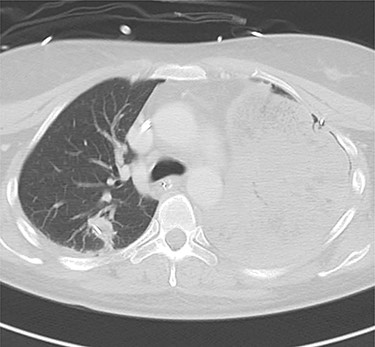

A 38-year-old woman with schizophrenia committed suicide by a self-infliction of sharp force into the chest and abdomen. She presented to our hospital in a critical condition. On arrival in the emergency room (ER), she developed hemorrhagic shock, which leads to an emergent abdominal damage control surgery under general anesthesia. She lost cardiac activity in the operating room during exploratory laparotomy. A left-sided basal thoracostomy, cross-clamping of the descending thoracic aorta, and open cardiac massage were also performed. She received gauze packing at the bleeding point and temporarily close the abdomen and chest wall. After the surgery, she was transferred to the intensive care unit with mechanical ventilation and recovered from hemorrhagic shock. Two days later, a second-look laparotomy was performed. ER doctors verified the hemostasis and closed the patient’s abdomen and chest. On the same day, a chest radiograph revealed pulmonary atelectasis of the left upper lobe (Fig. 1). Computed tomography (CT) revealed alveolar bleeding, pneumonia and atelectasis of the left upper lobe (Fig. 2). Despite antibiotic therapy and repeated endobronchial sputum aspiration, radiologic findings were not improved. On the seventh postoperative day, she was referred to our department for suspected lung abscess. When compared to the chest CT images on the day of initial surgery, pulmonary torsion was suggested (Fig. 3A). The sagittal CT images were reconstructed, and the torsion of the left upper lung lobe was diagnosed (Fig. 3B). Therefore, an emergency left upper lobectomy was performed through a left thoracotomy. Intraoperatively, the left upper lung lobe was rotated clockwise and was hemorrhagically and congestive infarcted. Due to severe pulmonary congestion, it was difficult to obtain the surgical field of view. The pericardial sac was opened and the intrapericardial isolation of the left upper pulmonary vein was performed. To prevent separation of the thrombus and necrotic material in the left upper lobe, we first dissected the left upper pulmonary vein before resolving the torsion and performing the lobectomy. She had a complete pulmonary fissure. Moreover, only one first pulmonary artery branch had ruled the approximately pulmonary arterial flow of her left upper lobe. The left upper lobectomy was performed. The patient made an uneventful recovery.

Computed tomography images of 2 days after initial emergency operation.